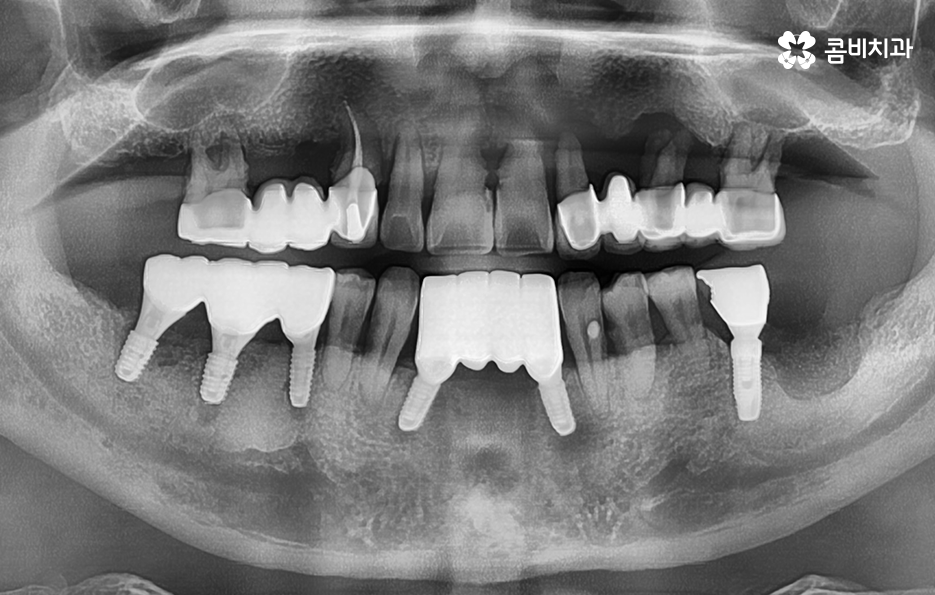

위 환자분의 케이스는 치주염이 심해져서 치아를 잃게 되기도 했지만 윗니의 경우 브릿지로 치아 기능을 유지하다가 결국 임플란트를 하게 된 사례로 볼 수 있어요

과거에는 임플란트 치료 자체가 없어서 브릿지나 틀니와 같은 치료를 할 수 밖에 없었지만 브릿지와 틀니의 한계점은 치아의 기능적인 부분에서도 한계점이 분명하지만 그에 더해 치조골이 점점 내려 앉고 흡수된다는 점에서도 임플란트의 장점이 명확하다고 할 거예요

노인임플란트 해도 될지 고민하시는 분들이라면 그냥 치아 없이 살아갈지에 대한 고민보다는 브릿지나 틀니에 대한 선택지 사이에서 고민하시는 분들이 많을 수 있는데요

비용적인 부분을 제외한다면 노인임플란트 시술을 잘 받고 사후관리를 철저히 해서 수명 유지를 하는 것이 치아의 심미성부터 기능, 관리상의 편의성 그리고 치조골을 유지하는 것까지 다방면에서 장점이 더 크다고 말씀드릴 수 있어요